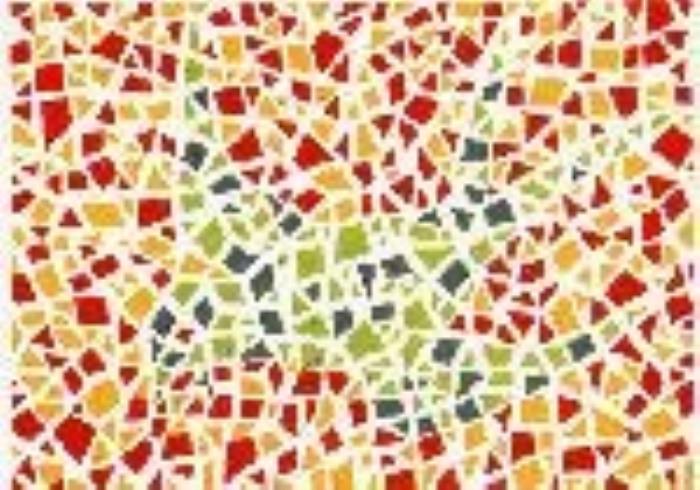

·形状图3

结果:正常看到的是一个圆形

·形状图4

结果:正常看到的是五角星(可以尝试离手机远一点看)